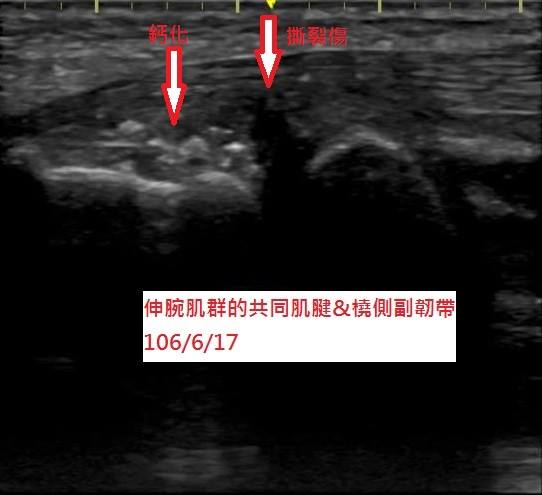

來到本院就診後,在高解析度超音波檢查下,發現他的右手伸腕肌群的共同肌腱有撕裂傷及許多鈣化(圖二),並不是單純的網球肘,難怪疼痛如此厲害。